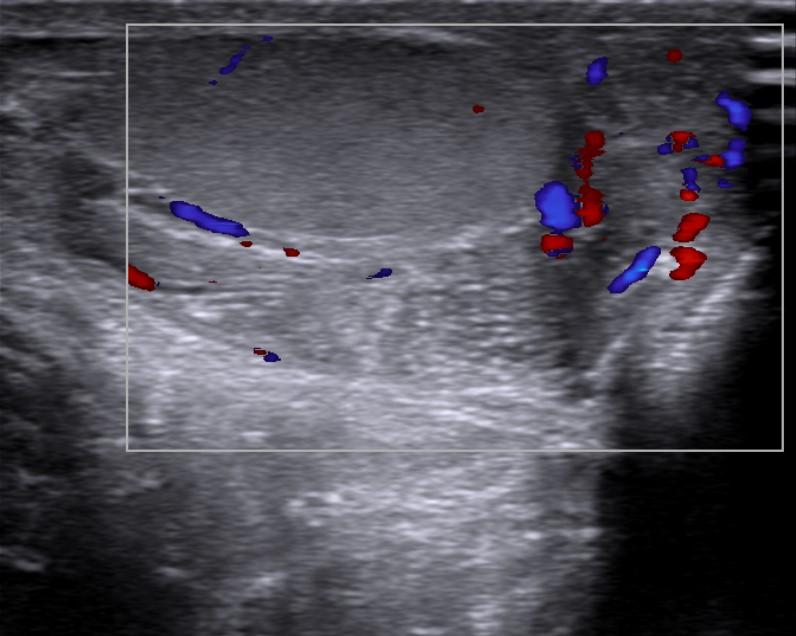

Case of the Week 31 2016 *33-year-old male with pain in left testicle. What is the most likely diagnosis? Answer Answer: Epididymitis Kategori:Cases Önceki yazı Case of the Week 6 2016 Sonraki yazı Case of the Week 17 2016